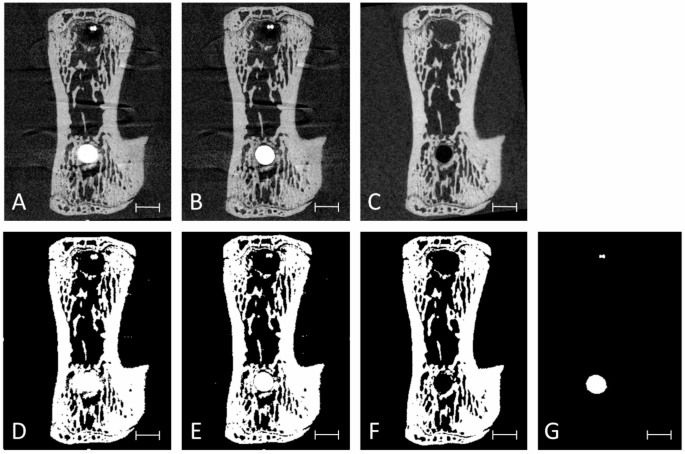

Visual validation

Visual inspection revealed a more evident reduction of metal artefacts on the peri-implant tissue after correction for the scan with implant, compared to the scan without implant (Fig. 4).

Representative transverse 2D slices of the same animal vertebra depicting (A) T0 scan, (B) \(\:{\text{T}}_{0}^{{\prime\:}}\) scan, (C) T1 scan, and (D-F) the segmentation of the respective scans above using a threshold of 29%. Peri-implant over-segmentation due to metal artefacts is visible in the T0 scan (D). Segmentation of Implants using a threshold of 85% in the T0 scan (G). Scale bar equal to 1 mm.

The results from the present study confirmed that voxels in close proximity to the implants were much more affected by metal artefacts compared to the more distant ones as described earlier11,22. Analysis of the computed correction coefficient revealed a logarithmic relationship between distance to the implant and peri-implant artefacts. By visual inspection of the CC (Fig. 1), the first 100 μm around the implant were most affected, whereas at increasing distance to the implant, the metal artefact induced elevation of grey values became lower. This result is in line with what reported in the canine study of Song et al.22 suggesting that a minimum distance of 50 μm from the implant surface is necessary for accurate BIC analyses, since regions closer than 50 μm are severely affected by major artefacts. The specific threshold yielding accurate segmentation may vary not only with distance to the implant, but also depending on implant geometry and material and other factors; however, as shown in Fig. 1, the corrected values were within a reasonable distance to the implant. A significant difference between the mean quotients before and after applying the CC was found. This could infer that, after applying the CC, the grey levels were closer to the grey levels of the dataset without the implant in place (T0). An approximation of the BV/TV values for the peri-implant bone could be achieved. In detail, when analysing the correction across the nine defined peri-implant bone regions, residual artefact values above zero in several regions indicated incomplete correction whereas, overcorrection, marked by values below zero, was observed only in few regions.

Different types of artefacts usually coexist, however in the present study they were not differentiated. Partial volume artefacts are hardly possible to correct owing to the incomplete information of the voxels’ reconstructed grey values. Also Compoton scatter is hard to detect solely by the approach presented here, but owing to the applied filtering, it is likely that Compton scatter had a minor impact on the results. Thus, it is assumed that the methodology presented mainly provided beam hardening correction, which occures due to the fact that a higher amount of photons is absorbed by metal compared to the bone, which eventually hardens the beam in proximity to the implant28. Consequentely it is likely that the produced images show artificially high attenuation in the surrounding bone, leading to elevated grey values in the peri-implant region. This phenomenon was particularly observed in the original grey scale images (T0) (Fig. 4A).